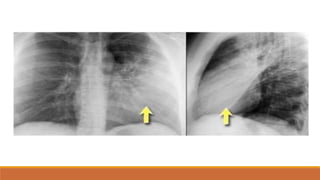

PHIM NẰM

MỜ LAN TỎA PHẾ TRƯỜNG VỚI BÓNG MẠCH MÁU VẪN CÒN

MỜ VÙNG ĐỈNH PHỔI VÀ NGOẠI BIÊN

MẤT BÓNG MỜ SẮC NÉT CỦA VÒM HOÀNH ĐỒNG BÊN

TÙ GÓC SƯỜN HOÀNH

DÀY RÃNH LIÊN THÙY BÉ